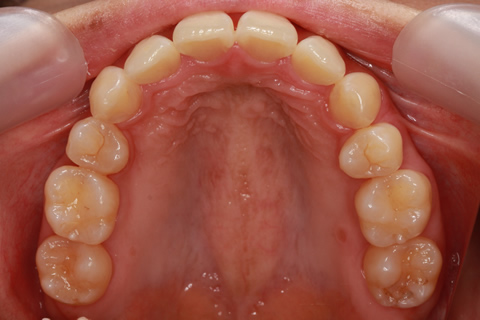

矯正期間24ヶ月

フルリンガル矯正1(上下の歯を舌側矯正で治療)

治療前

治療中

治療後

- 年齢・性別

- 33歳女性

- 治療期間

- 2年0ヶ月

- 抜歯

- 上顎4番抜歯。下顎5番欠損。

- 治療費

- 120万円(税込み)

- 備考

- フルリンガル矯正

- 治療内容

- 上顎前歯の叢生改善および下顎前歯の空隙閉鎖

- 施術の副作用(リスク)

- 装置が裏側について、目視ができないため、しっかりとブラッシングができているかどうかわかりにくい。